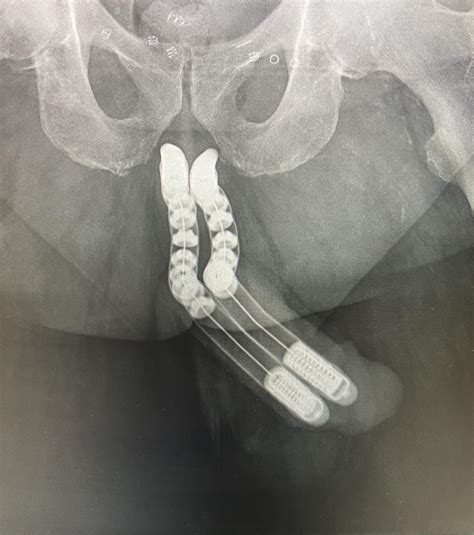

• Implants: Silicone or other materials are used to create implants that can be inserted into the penis to increase both length and girth.

• Surgical Technique: Depending on the chosen method, the surgeon will perform the necessary steps to increase the length or girth of the penis. This may involve cutting the suspensory ligament, inserting grafts or implants, or transferring fat.